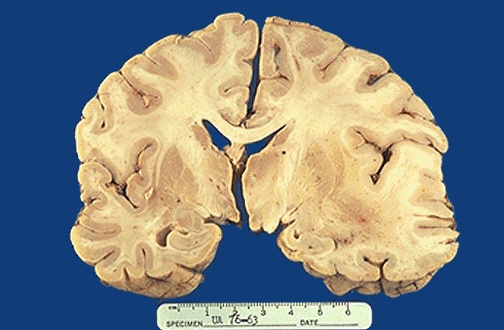

| There is cerebral edema seen at the right which obscures the structures. There is a shift of the midline to the left. Multiple small metastases were the cause for the edema in this case. [Image contributed by Jeannette J. Townsend, MD, University of Utah] |